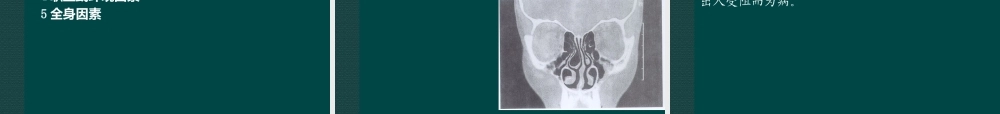

第四节急性鼻炎耳鼻喉科许黎耳鼻咽喉科学第八章鼻部疾病1阐述急性鼻炎的定义、诊断要点、治疗原则。2提示加自学本病的病因病理、临床表现、鉴别诊断、各种中西医治疗方法。3自学本病的实验室及其他检查、预防及调护、研究进展。教学内容重难点如下:掌握内容:掌握急性鼻炎的定义、临床表现、诊断要点、治疗原则。熟悉本病的病因病理、鉴别诊断、中西医治疗方法。了解本病的实验室检查,预防及调护。教学要求急性鼻炎急性鼻炎(acuterhinitis)病毒感染引起鼻粘膜急性炎症性疾病中医称“伤风鼻塞”,俗称“伤风”或“感冒”病因病毒感染,继发细菌感染诱因1全身因素尤其是过度疲劳和受寒凉刺激2局部因素鼻腔疾病,口腔,咽部感染急性鼻炎病理卡他性炎症;初期血管痉挛,腺体分泌减少继而血管扩张,充血水肿,腺体分泌增强晚期白细胞浸润明显,渗出而脱落坏死末期恢复病程约10天急性鼻炎病机正气虚弱,肺卫不固,风邪乘虚,侵袭致病风寒袭鼻多阳虚外感风寒风热犯鼻多阴虚肺有蕴热,外感风热;风寒化热急性鼻炎临床表现整个病程7~10天早期:病毒感染症状鼻塞清涕喷嚏咽部不适可伴有全身症状微恶寒,发热,乏力中期:继发细菌感染症状粘涕或脓涕后期:症状逐渐消失而愈急性鼻炎并发症经鼻窦开口-鼻窦感染经咽鼓管-中耳感染(不当擤鼻)向下扩散-咽,喉,气管支气管,肺部感染急性鼻炎诊断要点诱因特点:受凉及劳累史起病特点:起病急,病程短鼻部症状及全身症状鼻腔体征急性鼻炎鉴别诊断1变应性鼻炎-发作性,分期不典型,缺乏感染表现;变应原接触史2急性鼻窦炎-单侧性,急性感染症状突出,头痛,鼻腔体征急性鼻炎治疗改善鼻通气,促进鼻分泌物排出,预防并发症1局部治疗呋麻滴鼻剂,糖皮质激素喷鼻剂2对症治疗解热镇痛剂抗病毒药3合并感染加用抗生素4辨证论治5其他:单方验方:生姜葱白红糖水。针灸治疗:迎香,印堂等急性鼻炎辨证论治1风寒袭鼻证鼻塞,喷嚏,清涕,鼻音重,鼻粘膜略红,头痛,恶寒发热,口淡不渴,舌淡苔白,脉浮紧证候分析风寒外侵,肺气失宣,寒郁气道,鼻窍不利——鼻塞声重寒邪束表,阳气不宣——喷嚏寒凝津停,津气不行——涕多清稀寒为阴邪,阳气不宣——恶寒重发热轻头痛口不渴风寒外束——脉浮紧,苔薄白治法:祛风散寒,辛温通窍-辛夷散加减酌加苍耳子,鹅不食草急性鼻炎2风热袭鼻证:鼻塞,头痛,气热,涕粘黄,鼻粘膜红肿,发热恶风,微汗出,苔薄黄,脉浮数证候分析风热上犯,壅滞鼻窍——鼻塞气热邪热...